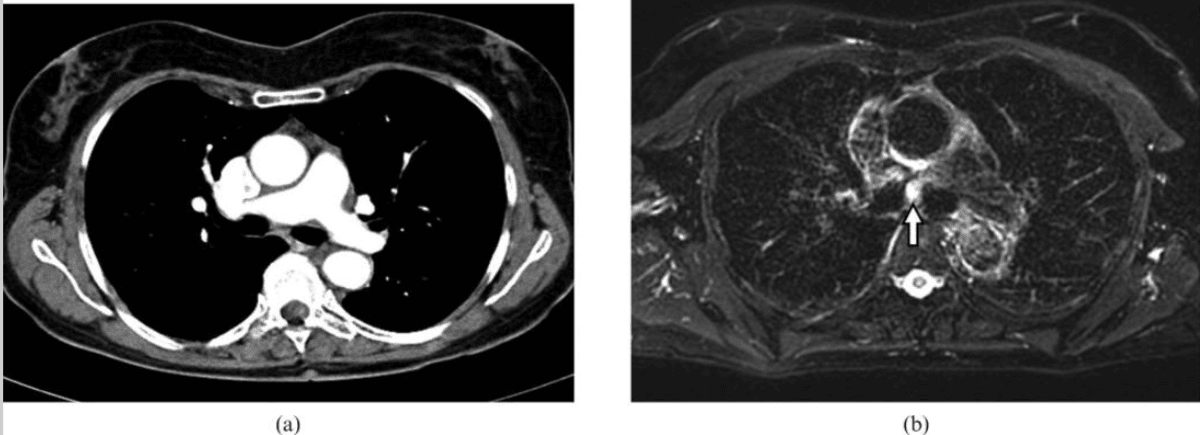

For patients with a known lung tumour, MRI excels at clarifying whether cancer has invaded the chest wall, mediastinum, or major vessels, such as the aorta, pulmonary artery, or superior vena cava5,6. High-resolution soft-tissue imaging is crucial for surgical planning, enabling surgeons to determine whether less invasive surgery is feasible or if open surgery should be avoided.

A key strength of MRI lies in its ability to reveal how the tumour relates to nearby structures such as major blood vessels, airways, and the pleura6,30. Clear imaging of tumour extension or invasion determines whether the lesion can be safely removed by surgery or if vital structures are involved, making surgery unfeasible.